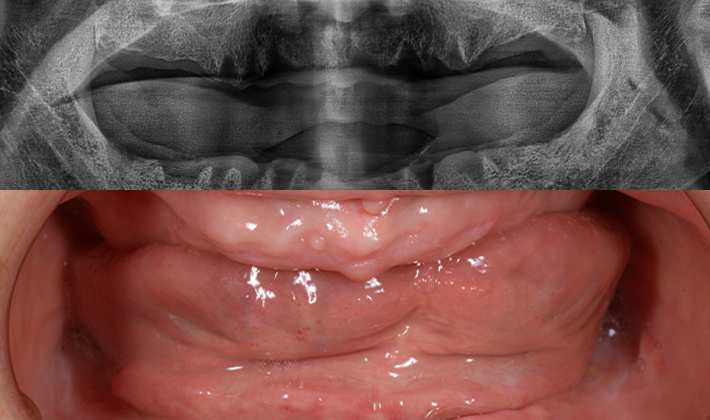

치과가 무서워 10년 동안 미뤄온 임플란트 수술 그 결과는?